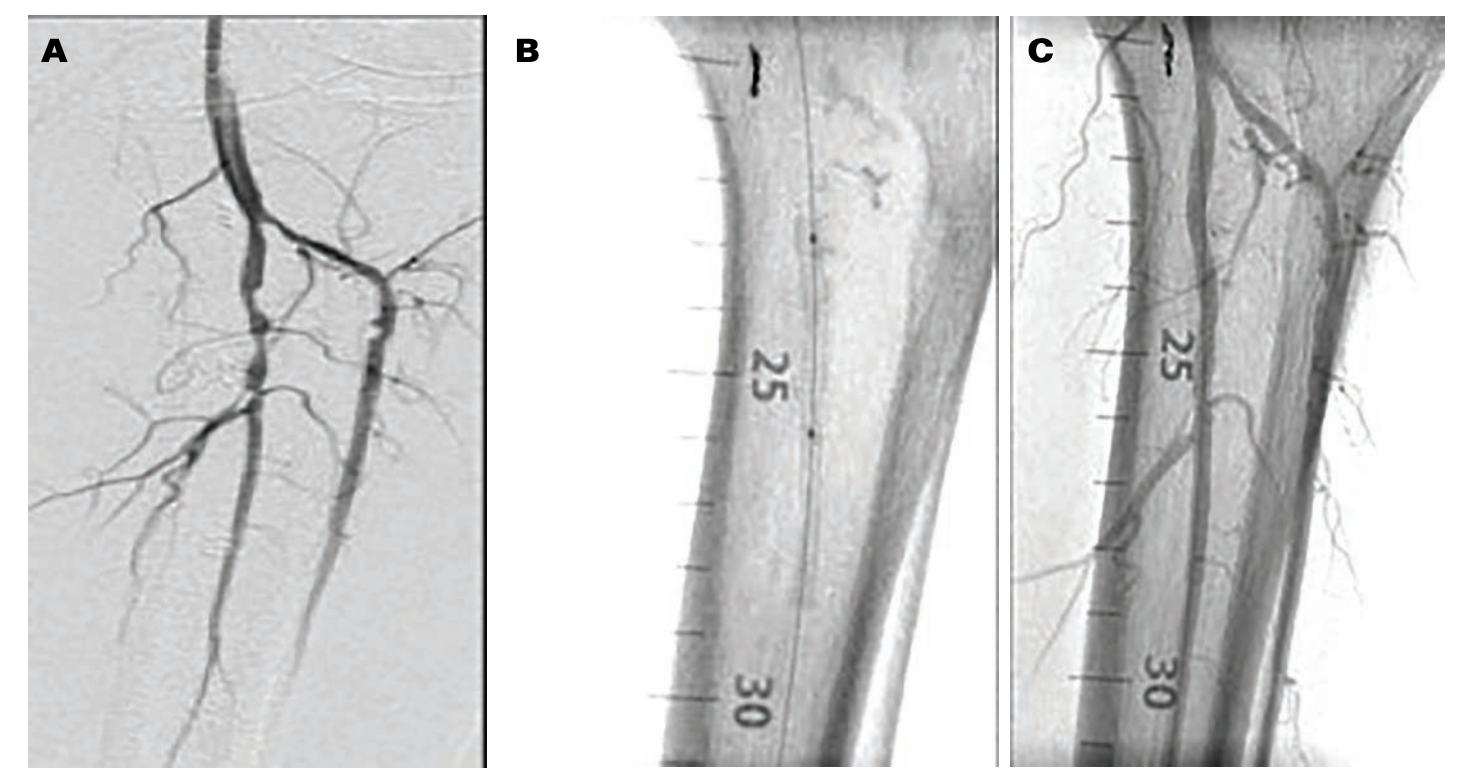

The STAND trial is in the early enrollment phases with the first patient enrolled in early April 2020. Figure 1 describes this case, which mirrors the high-risk demographic #CLIFighters evaluate and treat to prevent amputation and thus reduce mortality. We look forward to the 30-day follow-up, which is pending at the time of authorship.